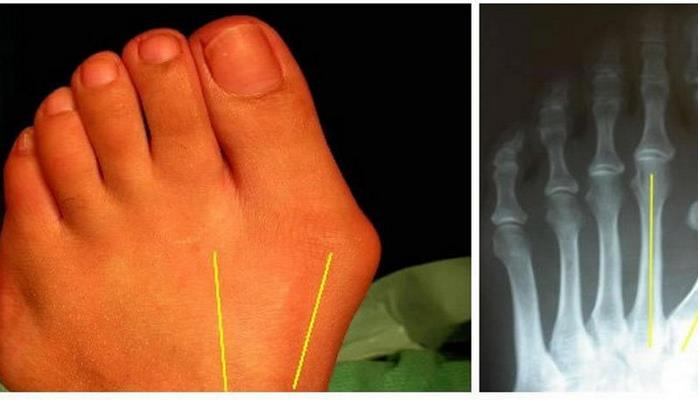

Симптомами вальгусной деформации стопы является отклонение большого пальца в сторону других фаланг, увеличение косточки, загибание к полу остальных пальцев, боль в суставах фаланг и повышенная утомляемость ног.

В качестве методов диагностики предписывается консультация у ортопеда, рентгенография и выявление плоскостопия.